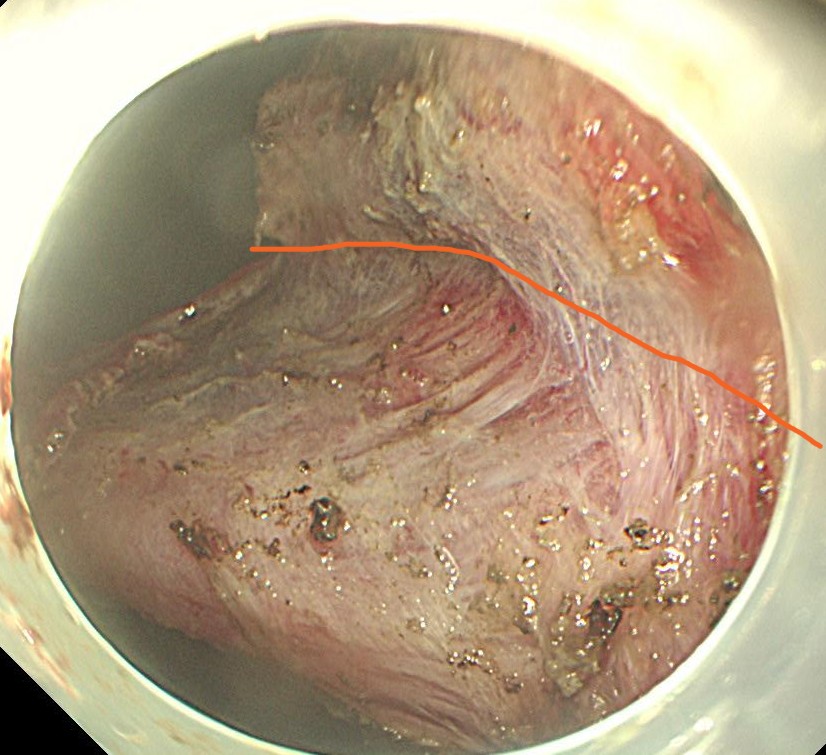

まずは腫瘍を取り囲むようにマーキングします。バイオ300のソフト凝固でマーキングしています。

マーキングの外側で全周切開します。フラッシュナイフを用いています。

オレンジのラインで切除していきます。